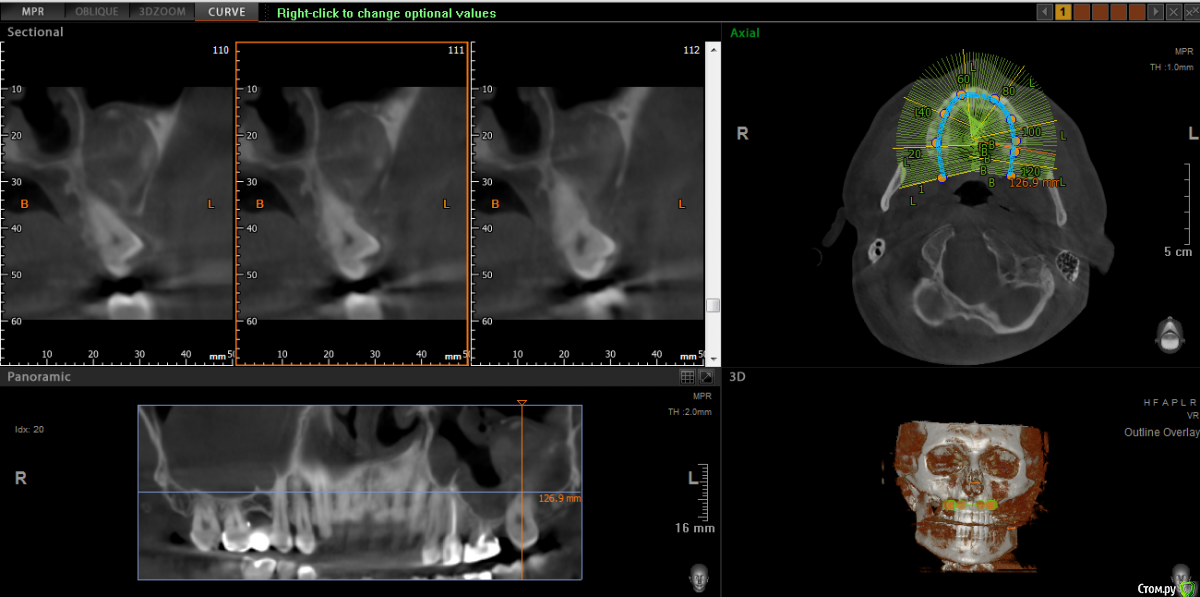

wladdX Опубликовано 5 марта, 2019 Поделиться Опубликовано 5 марта, 2019 Корональная проекция Сагиттальная справа Сагиттальная слева 16 26 28 Ссылка на комментарий

kramer Опубликовано 5 марта, 2019 Поделиться Опубликовано 5 марта, 2019 В общем скачал я КТ. Что касается зуба 26, да, там есть признаки воспаления вокруг корней, лечить / удалять зависит от состояния тканей зуба и возможностей врача. Но лично мне не кажется, что этот зуб играет главную роль в возникшем гайморите. Обратите внимание, в области 8 зуба (см. срез) внутри пазухи есть некий очаг, содержащий неоднородные по плотности элементы (более светлые включения, а выше пузырьки воздуха). Снимок не особо четкий, но такое ощущение, что в области 8 зуба вообще нарушена целостность боковой стенки пазухи. Кроме того, с правой стороны все зубы в порядке, а явления гайморита тоже имеются (там вообще почти вся пазуха забита). Соустья с носом закрыты. В общем, в данной ситуации я бы более детально обследовал 8 зуб, если там все нормально, то пусть ЛОРы эндоскопически лезут в пазухи и убирают это все. Ссылка на комментарий